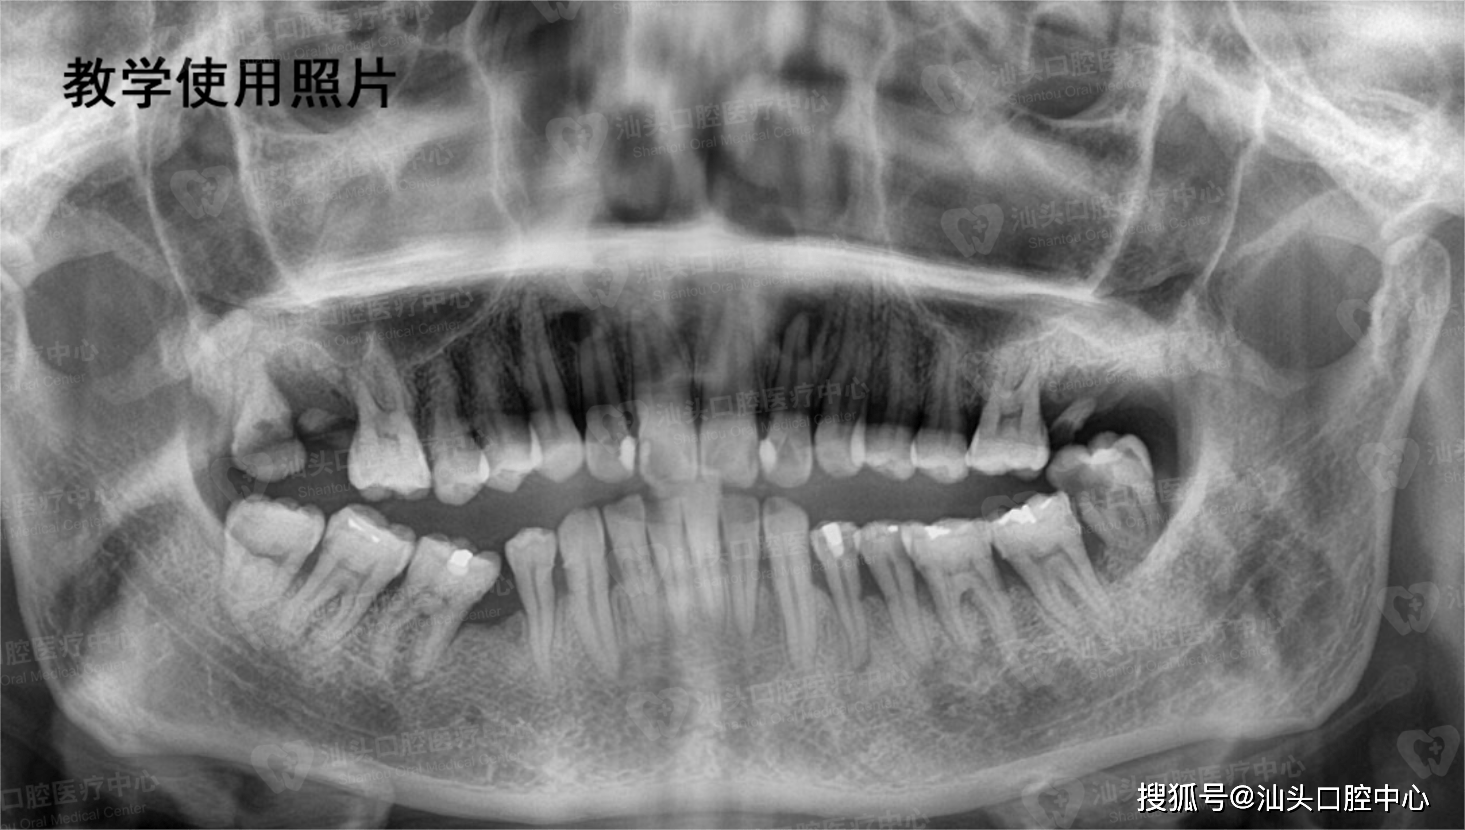

如果你的全景片上,智齿也是这样紧紧地"依偎"着7号牙(最后一颗磨牙)

拍摄"全景片",有时还会拍摄口腔cbct,预估智齿的位置,牙根数目及形态

什么是口腔全景片

全景牙科 x 线,全景 x 射线的口,具有完整的智齿: 全景摄影,也被称为